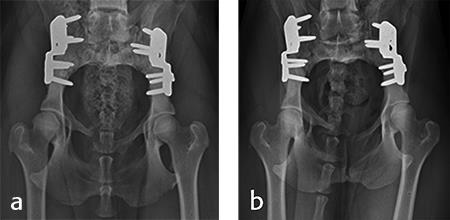

Postoperative radiographs revealed reduction in subluxation with capture of the femoral head in the right coxofemoral joint (Fig 4). Palpation of the hip revealed good stability of the right hip. Activity was restricted to leash walk only for 6 weeks postoperatively. Radiographic examination 7 weeks following surgery revealed healing of the ilial osteotomy, stable implants, and excellent coxofemoral conformation and stability (Fig 5).

Radiographic examination at 6 months postsurgery revealed stable implants, excellent coxofemoral conformation, and no evidence of osteoarthritis of the right hip. The left acetabulum was mildly shallow and mild subluxation of the femoral head was present at follow-up examination (Fig 6). Early osteophytosis in the region of the left femoral neck was evident. The dog was using the right hind leg normally and was showing no signs of instability or pain of the right hip. Mild instability and pain of the left hip was present on palpation. The dogs left hip was treated with a joint supplement and NSAIDs as needed. Future THR will be performed if clinical signs no longer respond to medical treatment.

Activity was restricted to leash walks for 6 weeks postoperatively. The radiographic examination 1 month after each surgery revealed partial healing of the ilial osteotomy and stable implants. Postoperative radiographs at 6 months after both surgical procedures revealed complete healing of the ilial osteotomies, stable implants, and excellent coxofemoral conformation, with no subluxation of the femerol head. Mild osteoarthritis was observed, however. At both the 4 and 6 month evaluation, the dog was using both hind limbs without any evidence of lameness and was showing no signs of instability or pain of either hip (Fig 10).